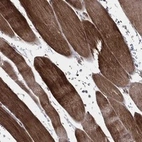

Immunohistochemical staining of human skeletal muscle shows strong cytoplasmic positivity in myocytes.